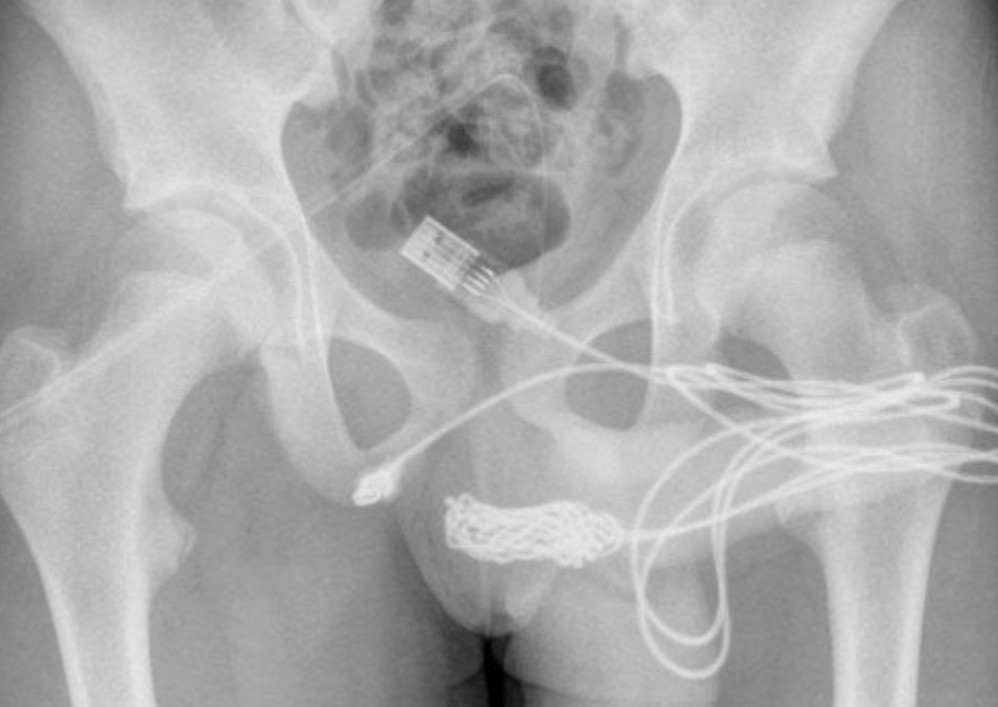

O adolescente foi com a família ao hospital mais próximo, mas tentativas manuais ou endoscópicas de remoção não foram eficientes porque havia um nó no cabo USB.

Ele foi então encaminhado ao University College Hospital London, onde há tratamento especializado e cirurgias urológicas. Os médicos precisaram realizar uma uretrostomia penoescrotal, onde é feito um corte entre a genitália e o ânus do paciente. O cabo foi cortado e retirado através de um meato uretral externo.